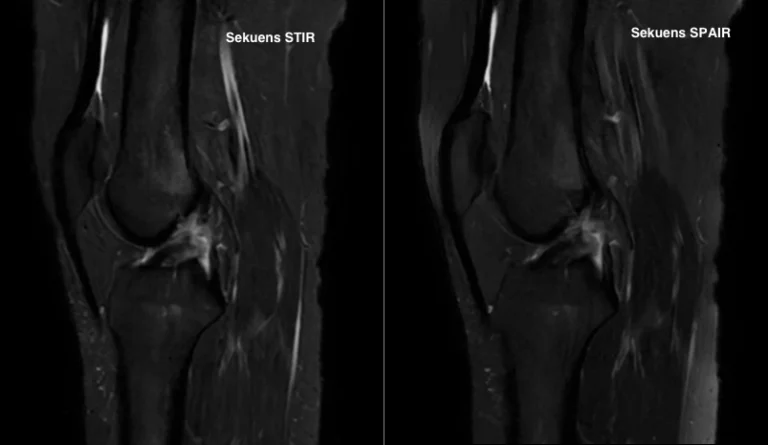

Sekuens T2 STIR dan T2 SPAIR merupakan teknik fat suppression yang umum digunakan. Sekuens T2 STIR menggunakan prinsip inversion recovery non selektif. Teknik ini mampu menekan sinyal lemak secara homogen pada seluruh area pencitraan.

Keunggulan utama T2 STIR adalah kestabilannya terhadap ketidakseragaman medan magnet. Namun, sekuens ini memiliki nilai signal to noise ratio yang relatif lebih rendah.

Sementara itu, T2 SPAIR merupakan teknik penekanan lemak berbasis frekuensi selektif. Sekuens ini menargetkan jaringan lemak secara spesifik tanpa memengaruhi jaringan lain.

Hasil citra yang dihasilkan umumnya memiliki kontras yang lebih tinggi. Struktur anatomi tampak lebih tajam pada beberapa kondisi. Akan tetapi, sekuens ini sensitif terhadap ketidakseragaman medan magnet.

Penelitian ini bertujuan membandingkan kualitas citra sekuens T2 STIR dan T2 SPAIR. Evaluasi dilakukan pada irisan sagital MRI knee joint kasus rupture ACL.

Secara kualitatif, T2 STIR menunjukkan penekanan lemak yang lebih homogen. Visualisasi lesi rupture ACL tampak lebih konsisten.

Sekuens ini lebih toleran terhadap variasi medan magnet. Hal tersebut menjadikan T2 STIR lebih stabil pada berbagai kondisi pemeriksaan. Sekuens ini sesuai digunakan pada evaluasi muskuloskeletal.

Sekuens T2 SPAIR menunjukkan ketajaman struktur anatomi yang baik pada kondisi tertentu. Beberapa artefak dapat ditekan dengan lebih optimal.

Sekuens ini sesuai digunakan pada sistem MRI dengan homogenitas medan magnet yang baik.